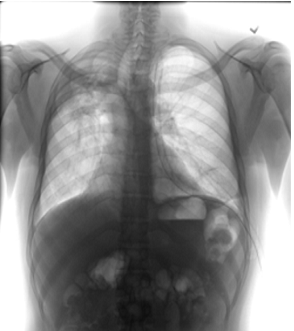

4.1 Qualitative Evaluation of Healthy Counterpart Generation

Example images from the disease COVID-19 Radiography Database and their generative healthy counterparts are given in figure 2. The images on the far left are instances of the lung opacity class from the real images in the dataset. The images in the middle column are examples of the generated healthy counterfactuals obtained via latent space diffusion, with RadBERT-guided textual-conditioning via a conditional prompt “normal chest x-ray”. A total of 75 diffusion inference steps are used with image conditioning strength=0.85 and guidance scale=7.5. (The former indicates the level of constraint on changes to the original input image and the latter is the weight given to the textual encoder conditioning in the generation of the image, ranging over [0,1] and [0,9], respectively).

Side-by-side inspection of the generated healthy counterfactuals (as per fig. 2) suggests that, as required, only minimal perturbation is made to the original image with respect to healthy pixels -i.e. localized image sites without structural medical defects. (In the top row, the medical structural defect in the original image is due to a lung opacity, and characterized via a relatively complex interaction between the imaging modality and subject manifesting as ‘gaps’ in the corresponding portions of the lung scan). The healthy/non-healthy discrepancy maps in all of these cases are obtained via masked subtraction of the original image from the generated image (the ground truth segmentation masks correspond to the broad area of interest –i.e. the complete lung). The generated healthy tissue is thus a subset of the mask and is shown in the final column of fig. 2 for the respective cases.

In the context of a VANT-GAN[20]-based approach, this highlighted material constitutes the diagnostic counterfactual visual attribution, i.e. the selection of material relevant to the diagnosis of the unhealthy condition. Healthy counterfactual generation was performed for the complete datasets in the three unhealthy classes, i.e Lung opacity, Viral Pneumonia and COVID, examples of which are given in fig. 3 for the three classes (all of the generated healthy counterfactuals from this experiment can be found on https://huggingface.co/ammaradeel/diffusionVA). Visual inspection indicates that the generated counterfactuals are, in general, visually plausible with minimal perturbation made to the unhealthy image overall. Moreover, the healthy counterpart generation does not appear to unnecessarily affect aspects of the images unrelated to the medical condition, the model selectively making changes to the unhealthy regions in a structurally plausible manner, e.g. generating missing portions of the lung without generating extraneous lung material where it would be expected to normally exist (e.g. in the abdominal cavity).